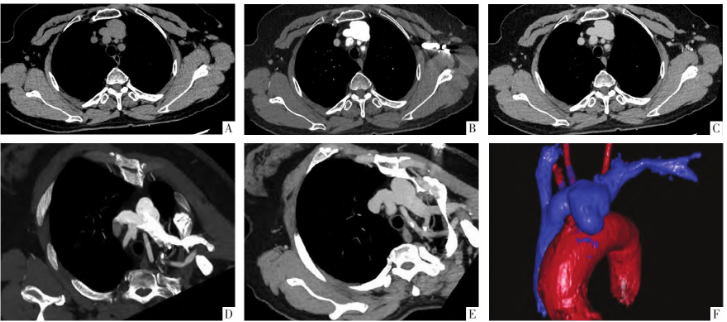

为进一步评估肿块与左侧无名静脉的关系,3 d后再次行CT增强扫描,此次对比剂经左侧肘前静脉注入,分别于20、120 s进行扫描。病人动脉期即可见病灶内对比剂充填,局部与邻近左侧无名静脉相交通;延迟期可见病变强化程度减低,其内密度均匀,密度与左侧无名静脉血管一致,瘤腔内无充盈缺损(图1D-I)。病例2仅行1次CT增强检查,对比剂经左侧肘前静脉注射,同病例1的第2次增强CT表现一致(图2)。

图2 病人女,64岁。A图为CT平扫,可见上纵隔肿块,密度均匀,CT值为47 HU,肿块边缘光滑,大小为2.3 cm×3.1 cm×3.9 cm,紧邻左侧无名静脉。B、C图为CT增强扫描(经左肘前静脉注射对比剂)的动脉期及延迟期,可见肿块于动脉期明显强化,延迟期强化程度减低,CT值分别为531、133 HU(同期相左侧无名静脉CT值分别为545、127HU)。D、E图为CT增强重建影像,肿块与左侧无名静脉相沟通。F图为伪彩图,可见肿块位于上腔静脉左侧,主动脉弓上方,其后方紧贴无名静脉。